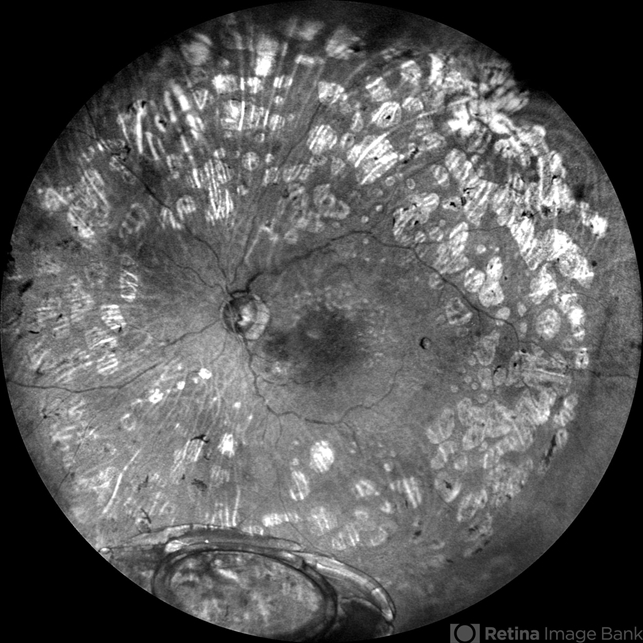

- dislocated IOL, dislocated intraocular lens (IOL), proliferative diabetic retinopathy (PDR)

- Scanning laser ophthalmoscope

- Grey color fundus photograph of the left eye of a 78 year old gentleman who has undergone pars plana vitrectomy for proliferative diabetic retinopathy, shows dislocated intraocular lens bag complex lying on the inferior retina